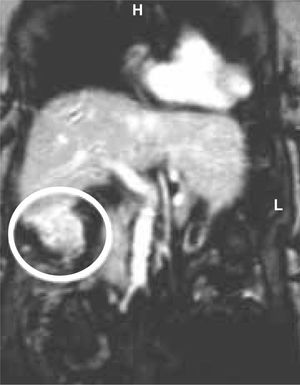

In September 2001, during follow-up at our outpatient liver unit we detected by ultrasound a hypervascular mass adjacent to the VI hepatic segment in a 78-year-old HCV-positive cirrhotic woman. Subsequently abdominal computed tomography (CT) revealed an infiltrative vascularized nodule (3.5 cm in diameter) at the lower border of the VI hepatic segment and magnetic resonance imaging showed a “tear-drop shaped” tumor (Figure 1A). Serum alpha-fetoprotein levels were normal (4 ng/mL), liver function was good (prothrombin time 84%, albumin 3.3 g/dL), without anemia and thrombocytopenia. No extrahepatic lesions were found.

The patient was discharged in good condition five days after surgery. Abdominal MRI performed one year later showed no signs of recurrence (Figure 1B). The patient is currently in good health, and her only medications are beta-blocker and lactulose.